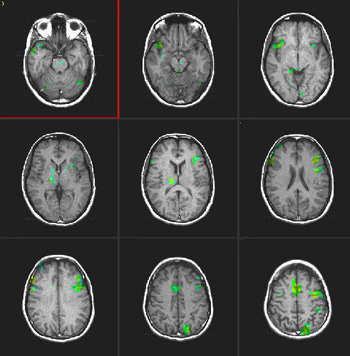

Inglés

|

(Hacer clic en las imágenes para agrandarlas)

| Activación |

Se observa una activación en el área de Broca en ambos idiomas. La activación talámica derecha se observa solo en el segundo idioma. Se observa también una mayor activación de la circunvolución frontal inferior derecha en el segundo idioma que en la lengua materna. El área motora suplementaria es más pronunciada en la derecha en ambos idiomas. |